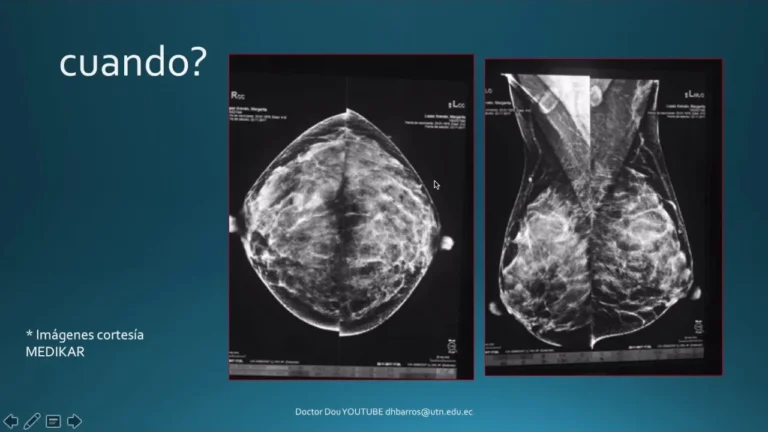

Slide 1 Lo que debes saber sobre las biopsias de mama Slide 2: ¿Qué es una biopsia de mama? Una biopsia de mama es un procedimiento que remueve un poco de tejido para analizarlo y determinar si hay la presencia…

Treat yourself right by getting A Mammogram Takes less time than a mani/pedi — and it can save your life The 5-year survival rate for localized breast cancer that’s caught early is 99% A Colonoscopy Not a massage, but you…